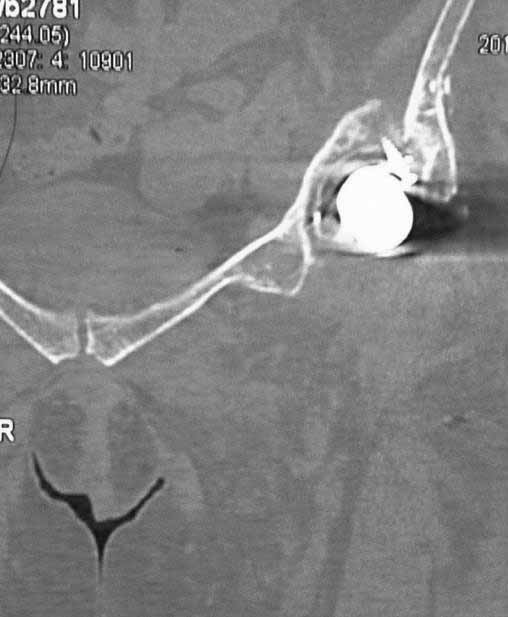

Уважаемые коллеги. Хотелось бы услышать мнения и советы по представляемому случаю.

Пациентка 45 лет. Бесцементное эндопротезирование левого тазобедренного сустава 6 лет

назад (впадина RM, Mathys, металл-металл, ножка Зульцеровская). За 10 лет до

протезирования коррегирующая остеотомия бедренной кости, которая не срослась в течение

года до удаления пластины, а затем срослась в течение 3 месяцев иммобилизации в кокситной

повязке. После протезирования получилось наблюдать пациентку почти постоянно, поскольку

через 2 года синтезировал ей лодыжки на оперированной стороне, затем, через несколько

месяцев удалил фиксаторы, а в 2009г. резецировал мениск на противоположной стороне. Боли

все эти годы не беспокоили. Пациентка чуть выше среднего роста, вес тела нормальный.

Физические нагрузки переносила хорошо. Работает на 7 этаже без лифта. Год назад экстирпация

матки по поводу лейомиомы больших размеров. Несколько месяцев назад появились боли в

области левого тазобедренного сустава. При рентгеновском и КТ исследованиях (июль с.г.)

нестабильность тазового компонента. От предложенной замены протеза пациентка на тот

момент, слава богу, отказалась. Через какое то время боли в области левого тазобедренного

сустава практически полностью прошли, а около 2 месяцев назад появилось ощущение

патологической подвижности таза и боли в паху справа, которые через некоторое время

уменьшились, а потом снова усилились после значительных физических нагрузок (много ходила

по песку на пляже, носила тяжести). Ежедневно принимала диклофенак. На рентгенограммах

переломы правой лонной кости. Сейчас госпитализирована из-за болей в паху справа. Боли

слева не беспокоят. На фоне снижения нагрузок в стационаре боли значимо уменьшились.

-Если думать о ревизии, то когда? На представленных снимках тазобедренный сустав до и

сразу после операции, затем 2 снимка 2009г., когда ничего не беспокоило, затем КТ 2-х

месячной давности и вчерашние рентгенограммы обоих тазобедренных суставов.